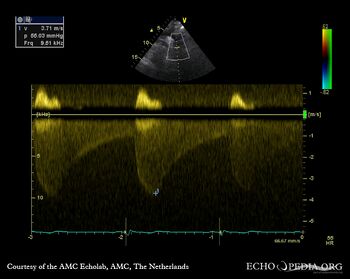

| Suprasternal view, Color Doppler in a patient with coarctatio aortae | Continuous-wave doppler: high velocity flow in descending aorta, sawtooth phenomenon |